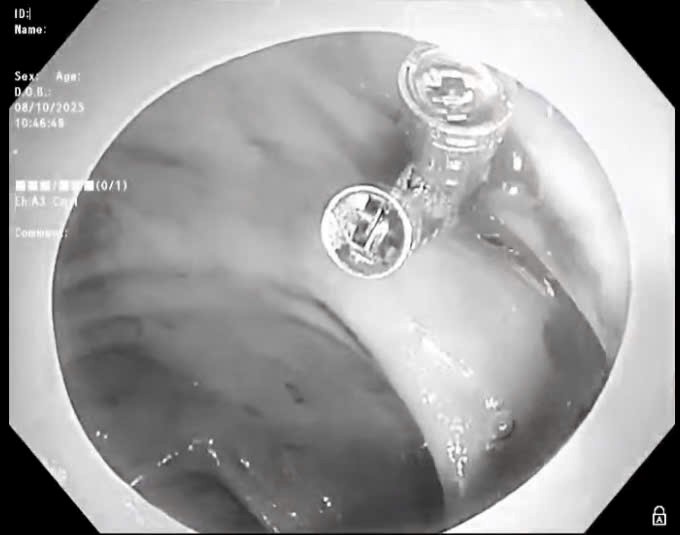

Quảng Trị: Kịp thời lấy viên thuốc nguyên vỏ bao kẽm kẹt ngang thực quản người bệnh

Thứ Tư, ngày 07/01/2026 02:38Ngày 6/1, Bệnh viện Hữu Nghị Quảng Bình, tỉnh Quảng Trị cho biết, vừa xử trí thành công 1 trường hợp bị dị vật thực quản đặc biệt, là viên thuốc còn nguyên trong bao kẽm. Dị vật gây đau...